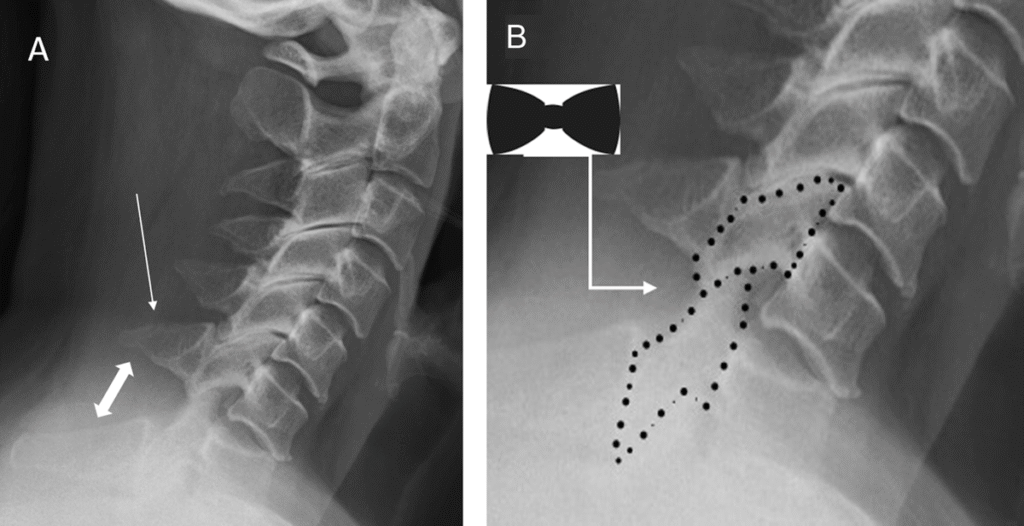

- Bán trật khớp: Các diện khớp của một đốt sống bị di lệch nhẹ về phía trước, đè lên bề mặt diện khớp của đốt sống bên dưới. Tình trạng này dẫn đến sự di lệch nhẹ ra phía trước của một thân đốt sống so với đốt sống kia.

- Trật khớp hoàn toàn: Sự di lệch của một khớp liên mấu khiến phần diện khớp tiếp hợp trượt qua toàn bộ bề mặt khớp và bị khóa lại ở vị trí này.

Trật khớp có thể xảy ra một bên (liên quan đến một diện khớp) hoặc hai bên (liên quan đến cả hai diện khớp ở mỗi bên cột sống). Trượt đốt sống do chấn thương (nơi toàn bộ thân đốt sống trượt lên trên đốt sống bên dưới) có thể là kết quả của trật khớp liên mấu cấp tính.